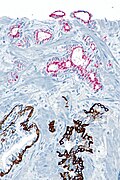

IHC

Usually stains like cancer:

- AMACR +ve.

- CK34betaE12 -ve.

- p63 -ve.

Note:

- Often not contributory.